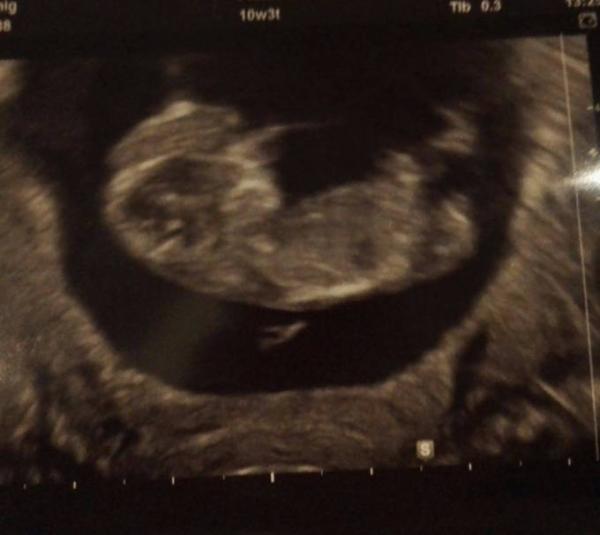

Hatte um 11:30 Uhr den Termin und kam dann endlich um 12:30 Uhr dran. Ich sag euch, das war psychische Folter!! Aber wir wurden zum Glück mit einem 4 cm großen Krümel entschädigt!! Es ist alles da wo es sein soll, die Nackenfaltenmessung macht meine FÄ automatisch mit. Auch die war unauffällig. Ich bin so erleichtert und kann es nun langsam auch glauben, nochmal Mama zu werden! Wünsch euch einen schönen Nikolaus

Das sind doch schöne Nachrichten. Ich freu mich für dich. Genieße jetzt die Vorweihnachtszeit. Ich habe meinen Termin am 12.12. Bin auch schon gespannt P.s. superschönes Bildchen von deinem schatz

Ein super schönes Foto von eurem Krümel habt ihr da

Jetzt sieht es immer mehr aus wie ein Baby. Wirklich schönes Bild.

Das Foto ist auch sehr gut und ich freue mich, dass deine Messwerte so gut waren.